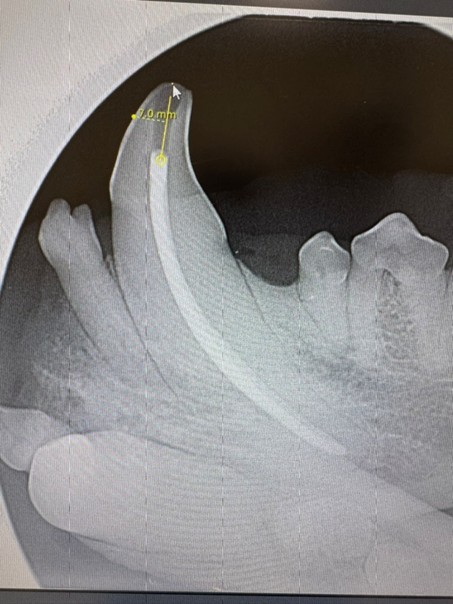

- Kanalverläufe, Krümmungen und anatomische Herausforderungen sicher einschätzen

| 09:15-11:15 Uhr | Mikroanatomie und Pathophysiologie am verletzten Zahn |

| 11:30-13:00 Uhr | Grundlagen der maschinellen Aufbereitung des Wurzelkanals |